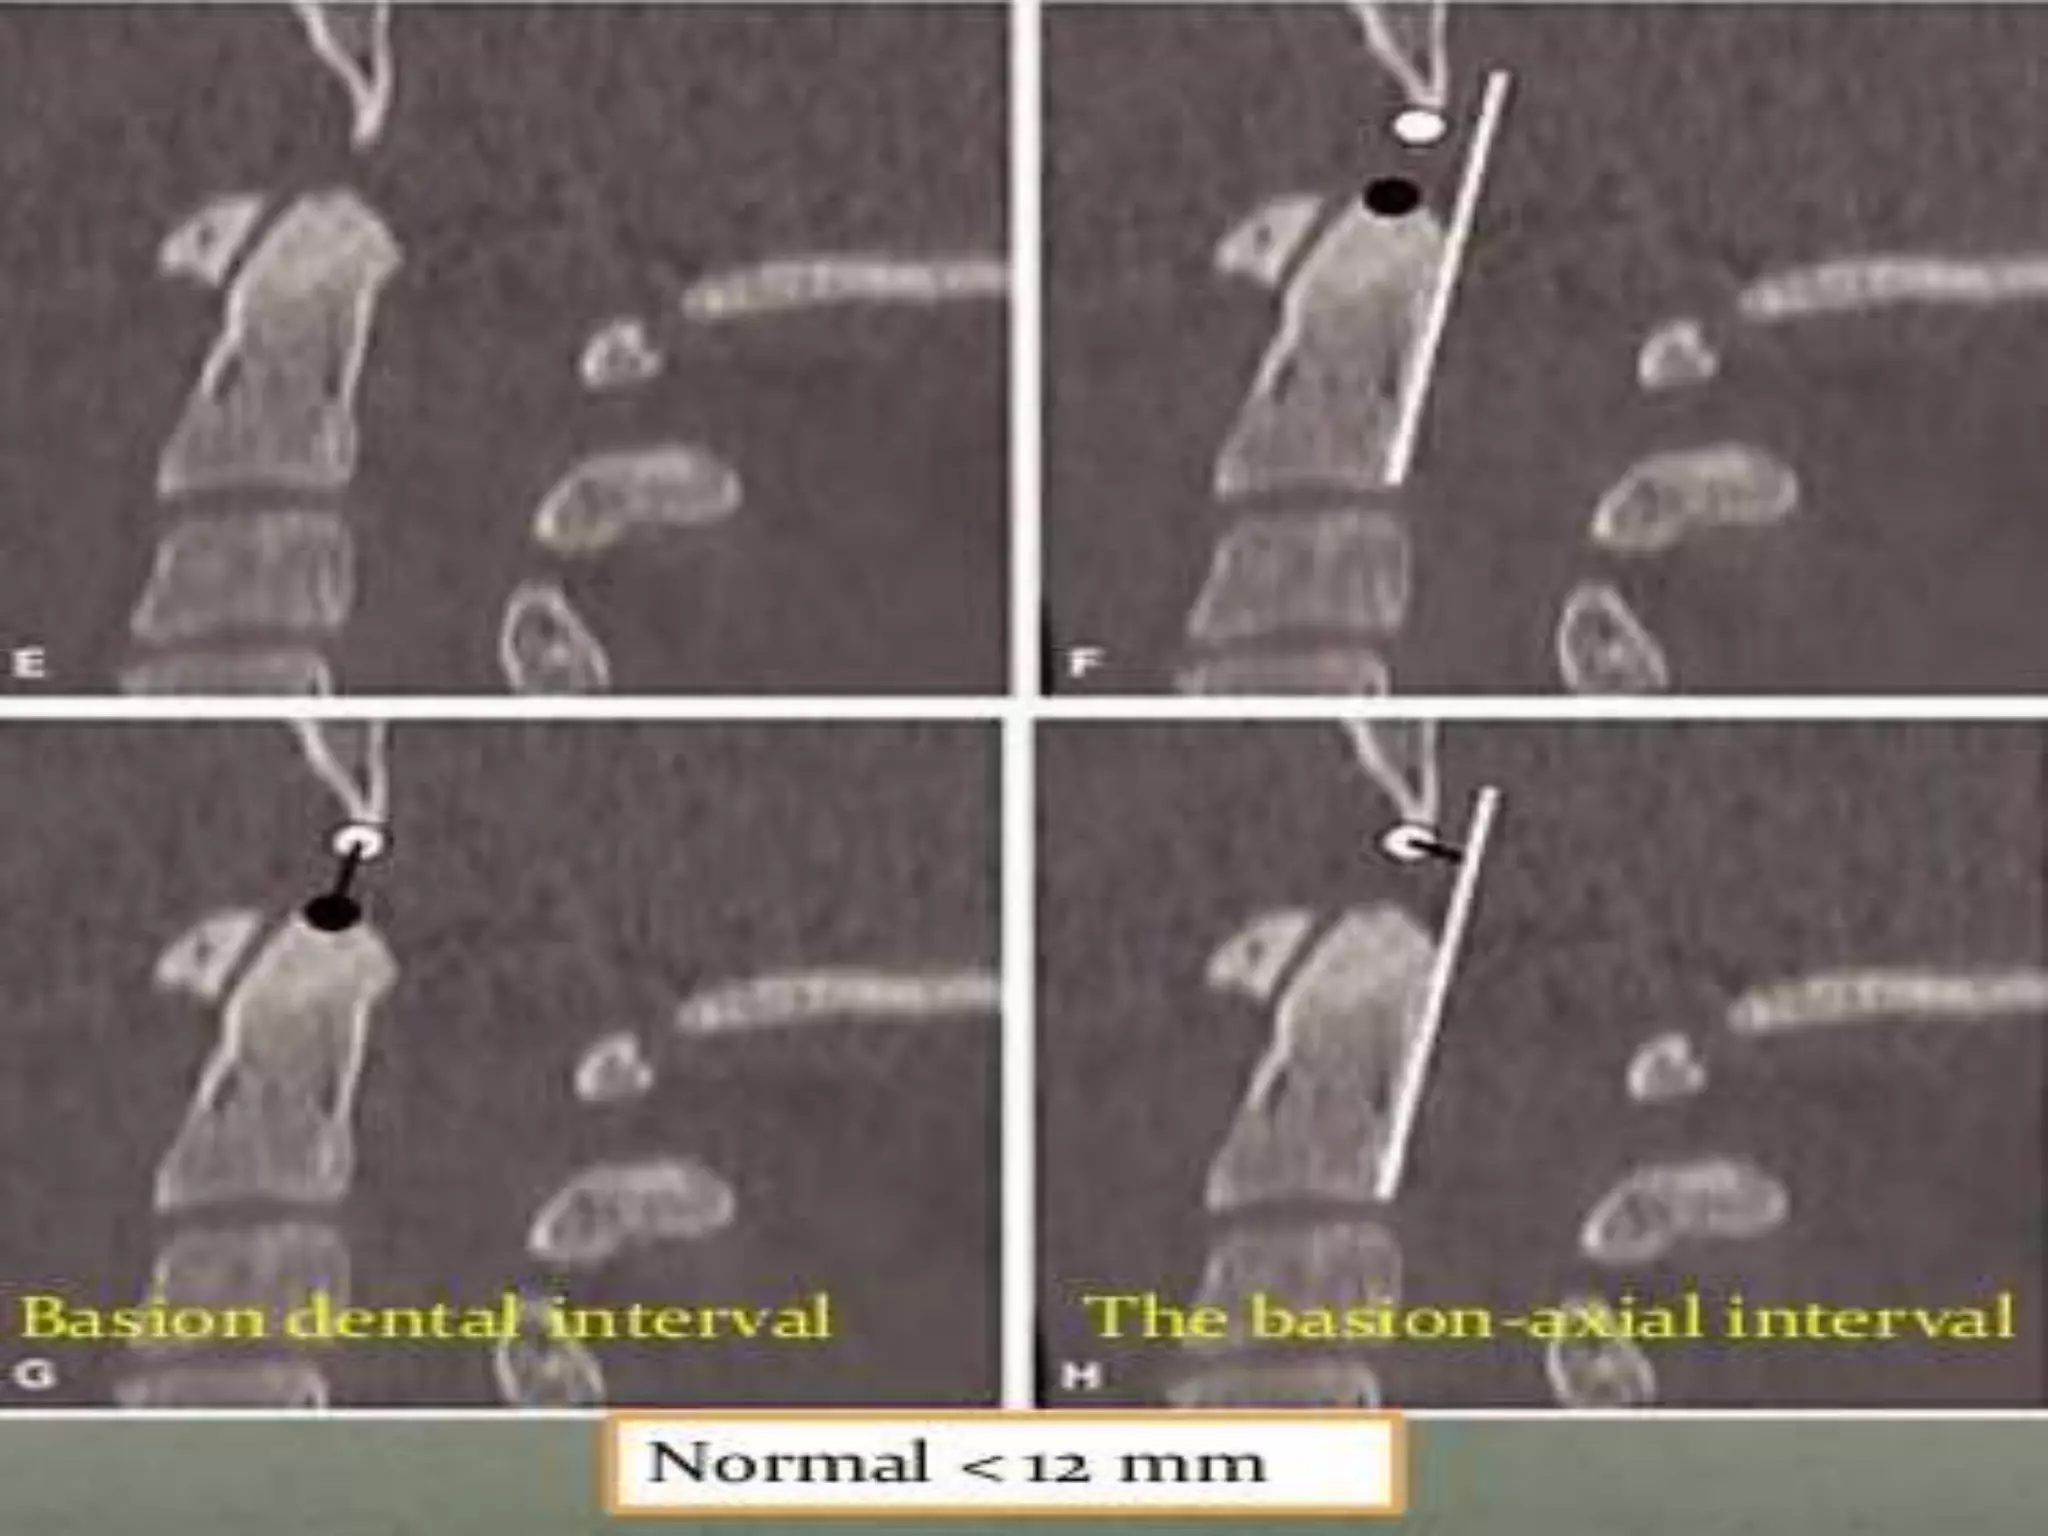

Transverse Atlantal

Ligament Rupture:

• Increased atlantodental space.

• Anterior translation of atlas and skull.

• Associated with Jefferson fracture.